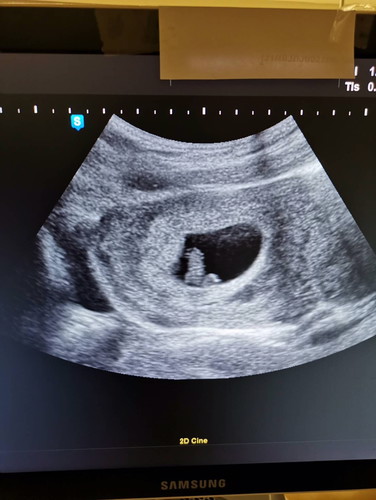

7 วีค 2 วันค่ะ

เห็นเจ้าตัวน้อย และหัวใจเต้นแล้ว ของคุณแม่ๆตอน7วีคเป็นอย่างไรกันบ้างค่ะ